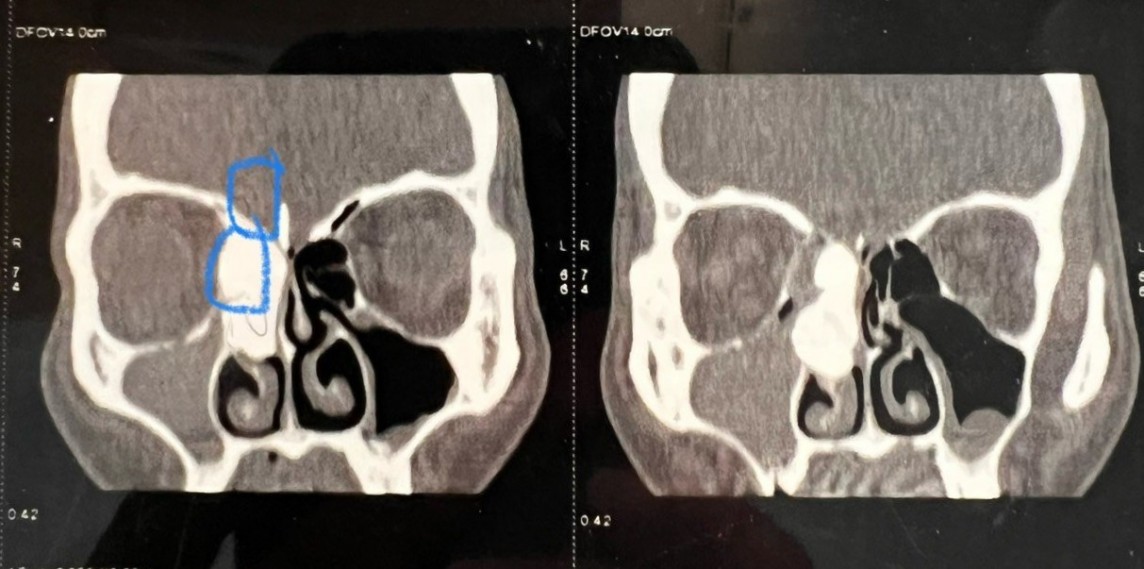

Ths. Bs Nguyễn Thị Thanh Bình - khoa Tai mũi họng và Phẫu thuật đầu cổ - Bệnh viện Đa khoa Hồng Ngọc cho biết: “Thông thường, khối u xương hốc mũi không hề hiếm gặp, thường là do răng đi lạc chỗ và có kích thước bé do không phát triển. Nhưng với bệnh nhân A., khối u lại rất lớn, chiếm toàn bộ hốc xoang sàng, trên CT scanner thể hiện khối u chạm tới màng não, bộc lộ cả nền sọ và mắt - thì lại cực kỳ hiếm gặp. Đời làm bác sĩ lần đầu tôi mới thấy trường hợp hy hữu này.”

| Hình ảnh CT scanner khối u xương chạm tới màng não, bộc lộ cả nền sọ và mắt |